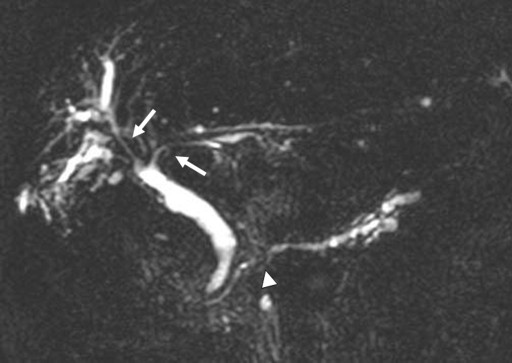

Seven years after clinical onset, abdominal CT revealed multiple pancreatic stones in an atrophic pancreas (Figure 2). ERCP (Figure 3) and magnetic resonance cholangiopancreatography (MRCP) (Figure 3) revealed stenosis of the main pancreatic duct in the head of the pancreas and upstream dilatation. MRCP (Figure 4) and ERC (Figure 5) revealed a longer stretch of stenosis in the hilar hepatic region. We tried steroid therapy in an attempt to ameliorate the stenosis of both the bile duct and the pancreatic duct, and prevent further progression. The initial dose of prednisolone was 30 mg, and this was gradually reduced. Two weeks, 7 weeks, and 11 weeks after the start of prednisolone administration, MRCP revealed no improvement of either the bile duct stenosis or the diffuse irregularity of the main pancreatic duct. The atrophic pancreas showed no change in size. The serum IgG and IgG4 levels decreased from 1,463 to 756 mg/dL (reference range: 870-1,700 mg/dL), and from 127 to 32.9 mg/dL, respectively. The steroid therapy was therefore stopped because of its ineffectiveness and the worsening of diabetes mellitus.

Figure 4. Magnetic resonance cholangiopancreatography showing long strictures in the hilar hepatic region (arrows), stenosis of the main pancreatic duct in the the head of the pancreas (arrowhead) and upstream dilatation. |